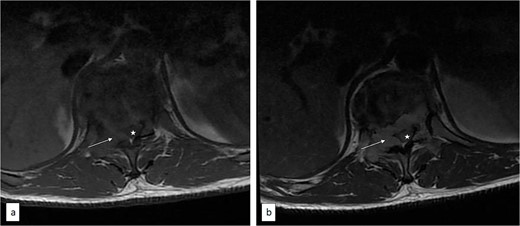

Thoracic spine MRI showed collapsed T11 vertebral body (Fig. 1), T1 isointense and T2 hyperintense extradural mass compressing the spinal cord and involving the posterior elements (Figs 1 and 2). There was no radiological evidence of metastatic lesions. He subsequently had T10–12 laminectomy, near total tumour excision, and spinal stabilization with rigid vertical strut and spinal process wire [8]. The tumour histomorphological and immunohistochemical features were consistent with NB.

Axial T1 pre (a) and post (b) contrast thoracic spine MRI showing contrast-enhancing extradural tumour (arrow) compressing the spinal cord (asterisk).